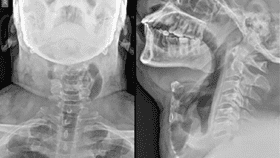

The neck inflation’s cause became apparent when doctors got him to play his trumpet during a CT scan. It revealed an area of his throat that was inflating abnormally whenever he forced out air.